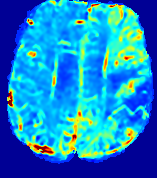

LesionRefer to captionRefer to captionRefer to captionRefer to captionRefer to captionRefer to caption𝐕rgbsubscript𝐕𝑟𝑔𝑏{\bf{V}}_{rgb}Refer to captionRefer to captionRefer to captionRefer to captionRefer to captionRefer to caption𝐕2subscriptnorm𝐕2{\|\bf{V}}\|_{2}Refer to captionRefer to captionRefer to captionRefer to captionRefer to captionRefer to captionRefer to caption3.53.53.52.82.82.82.12.12.11.41.41.40.70.70.70.00.00.0(mm/s)𝑚𝑚𝑠(mm/s)D𝐷DRefer to captionRefer to captionRefer to captionRefer to captionRefer to captionRefer to captionRefer to caption0.0200.0200.0200.0160.0160.0160.0120.0120.0120.0080.0080.0080.0040.0040.0040.0000.0000.000(mm2/s)𝑚superscript𝑚2𝑠(mm^{2}/s)Slice #1Slice #2Slice #3Slice #4Slice #5Slice #6

Figure 3: PIANO feature maps for one stroke patient, where the lesion is located in the left hemisphere. Top row: segmented stroke lesion region (white) on different slices, obtained from ISLES 2017. The corresponding slices for the PIANO feature maps are shown in the following rows.

For a better insight into an estimated velocity field 𝐕𝐕{\bf{V}} and diffusion field 𝐃𝐃{\bf{D}}, we compute the following maps: (1) 𝐕rgbsubscript𝐕𝑟𝑔𝑏{\bf{V}}_{rgb}: Color-coded orientation map of 𝐕=(Vx,Vy,Vz)T𝐕superscriptsuperscript𝑉𝑥superscript𝑉𝑦superscript𝑉𝑧𝑇{\bf{V}}=(V^{x},V^{y},V^{z})^{T}, obtained by normalizing 𝐕𝐕{\bf{V}} to unit length and mapping its 3 components to red, green, blue respectively; (2) 𝐕2subscriptnorm𝐕2\|{\bf{V}}\|_{2}: 222 norm of 𝐕𝐕{\bf{V}}; (3) D𝐷D: scalar field in Eq. 5.

Fig. 3 and Fig. 4 show the PIANO feature maps estimated from two ISLES 2017 patients: all are highly consistent with the lesion in both cases. Details of the blood flow trajectories are revealed in 𝐕rgbsubscript𝐕𝑟𝑔𝑏{\bf{V}}_{rgb} by the ridged patterns and the sharp changes of colors in the unaffected (right) hemisphere, while the flat patterns appearing within the lesion provide little directional information about the velocity and indicate low velocity magnitudes. Velocity magnitudes are more directly visualized via 𝐕2subscriptnorm𝐕2\|{\bf{V}}\|_{2}, from which one can easily locate the lesion where 𝐕2subscriptnorm𝐕2\|{\bf{V}}\|_{2} is low. D𝐷D also indicates lower diffusion values in the lesion, though with less contrast potentially due to the fact that it captures the accumulated effect of CA diffusion at the voxel-level.